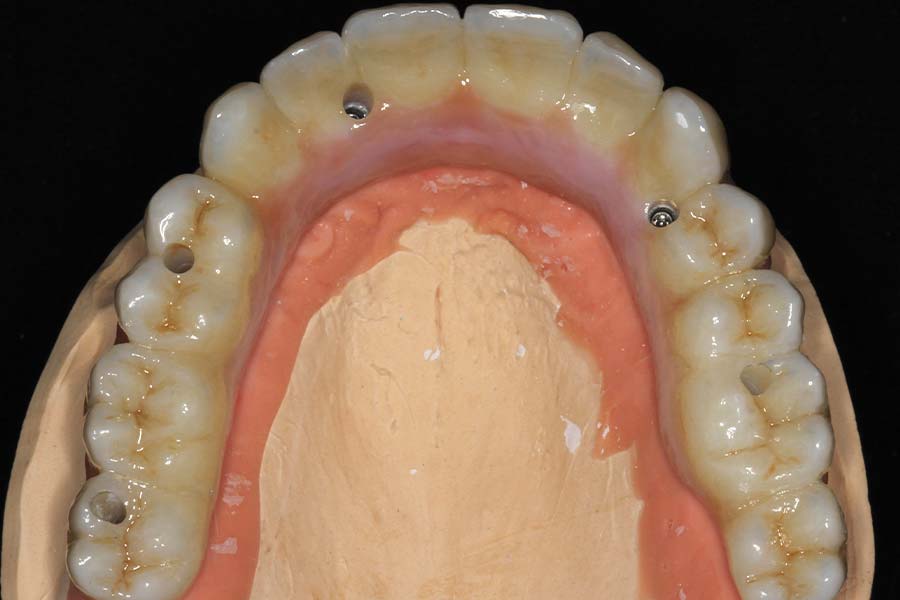

Occlusal (mirror) view of the upper implants. This patient had good bone in these five areas. If the bone was better we would have added a sixth implant.

Tissue-view of the final implant bridge. Note the convex (cleansable) contours. This is a wide departure from “All-on-4” treatment which is virtually uncleansable.